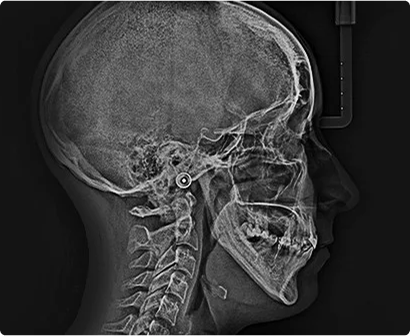

Zdjęcia profilowe - cefalometryczne

Dzięki posiadanej odpowiedniej przystawce w aparacie CS 9600 3D mamy możliwość wykonania zdjęć profilowych głowy – cefalometrycznych, zwanych potocznie CEFALO lub TELE RTG. Są to zdjęcia, których używamy dla potrzeb diagnostyki ortodontycznej

Posiadają one szczególną, techniczna zaletę jednoczesnego obrazowania profilu części kostnego szkieletu twarzy, jak i jego tkanek miękkich. Ukazują obrys skóry nosa ust, jak również bródkę.

Badanie cefalometryczne, zwane również profilowym lub tele RTG, polega na zobrazowaniu profilu czaszki uwzględniającym tkanki twarde i miękkie twarzy, podniebienie twarde oraz zatoki przynosowe. Projekcja ta niezbędna jest w ortodontycznej diagnostyce wad zgryzu, planowaniu ich leczenia, kontrolowaniu jego przebiegu oraz uzyskanych efektów.

To kilkusekundowe badanie wykonuje się za pomocą specjalnej przystawki do aparatu pantomograficznego – głowa pacjenta zostaje unieruchomiona przy użyciu uchwytów nakładanych na uszy i nos.